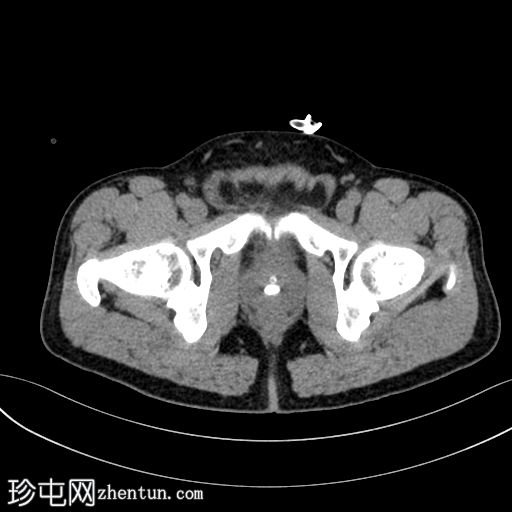

轴位

平扫

前列腺尿道内可见一枚较大的结石,大小约为10.5 x 13.5 x 7.5 mm(前后径 x 横径 x 头尾径)

轻度肾盂输尿管积水,左侧更为明显

膀胱壁轻度增厚约4 mm,膀胱周围脂肪间隙模糊,提示合并膀胱炎